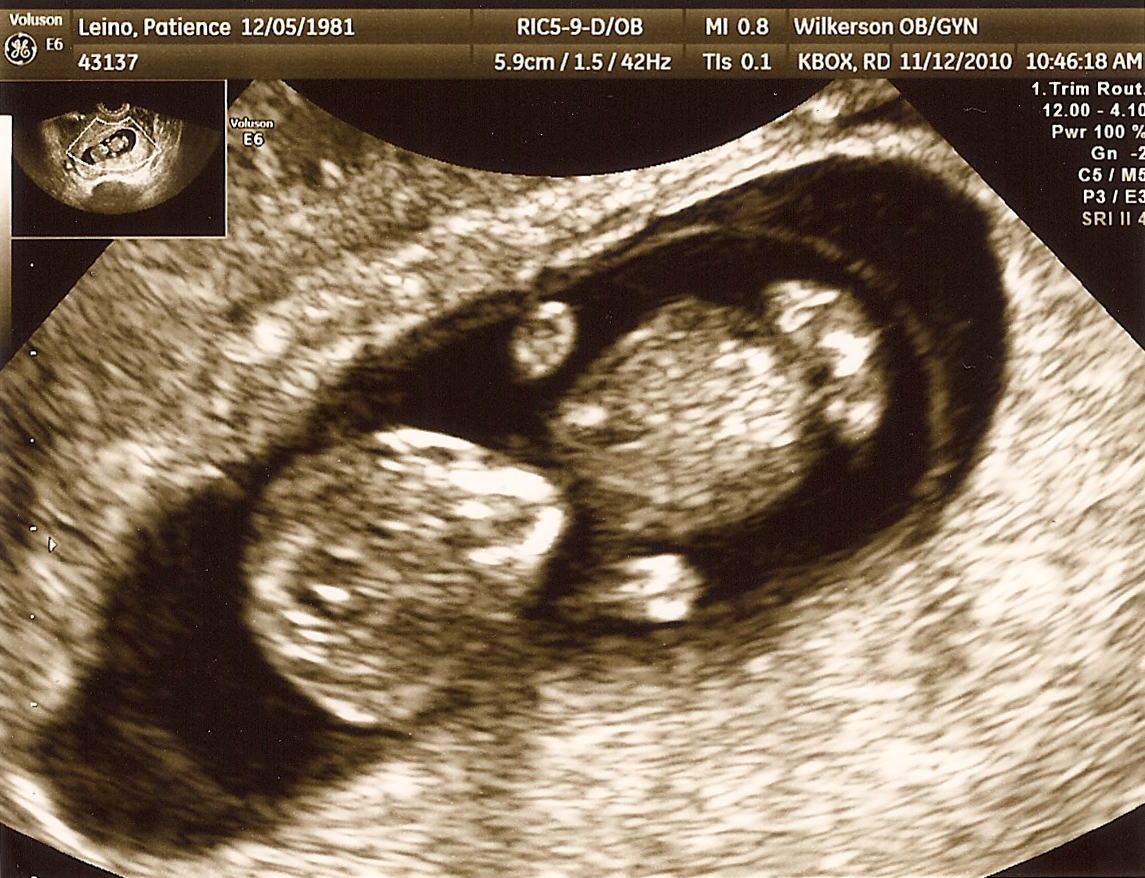

Today we saw our littlest bundle of joy again. As soon as his/her little body came on the screen, this pregnancy sank in to a whole new level. There’s a real little person in there! Our first sonogram a few weeks ago showed just a flickering dot. Its absolutely amazing how quickly babies develop. A mere three weeks later and our darling looked human! We saw legs, arms, spine & a sweet little noggin. Our official due date is June 4, 2011. So there you have it. Its officially official. We’re having a baby!

This is GREAT NEWS!! He/she is SOOOO CUTE already!!! Look at that belly!!! 🙂 Congratulations again!!! I rejoice with you!! ❤